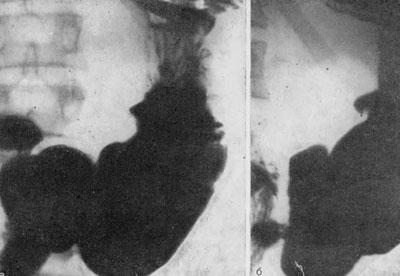

Само железо для рентгеновских лучей непроницаемо, так что выявить его можно лишь на обзорных рентгенограммах желудка. Подобным же методом производится подтверждение эффективности выбранной методики лечения.

Первым делом после попадания в больницу пострадавшему сделают рентгенографию живота, что позволит быстро обнаружить содержащие железо таблетки. Для проверки успешности лечения подобные снимки будут делать постоянно с некоторой периодичностью.